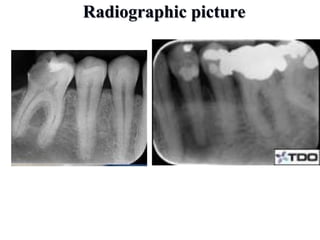

Radiographic picture

• #28 in the acute phase, no signs are observedat the bone (which may be observed 8–10 days later), unless there is recurrence of a chronic abscess, where upon osteolysis is observed. Radiographic verification of a deeply carious tooth or restoration very close to the pulp, as well as thickening of the periodontal ligament, are data that indicate the causative tooth.